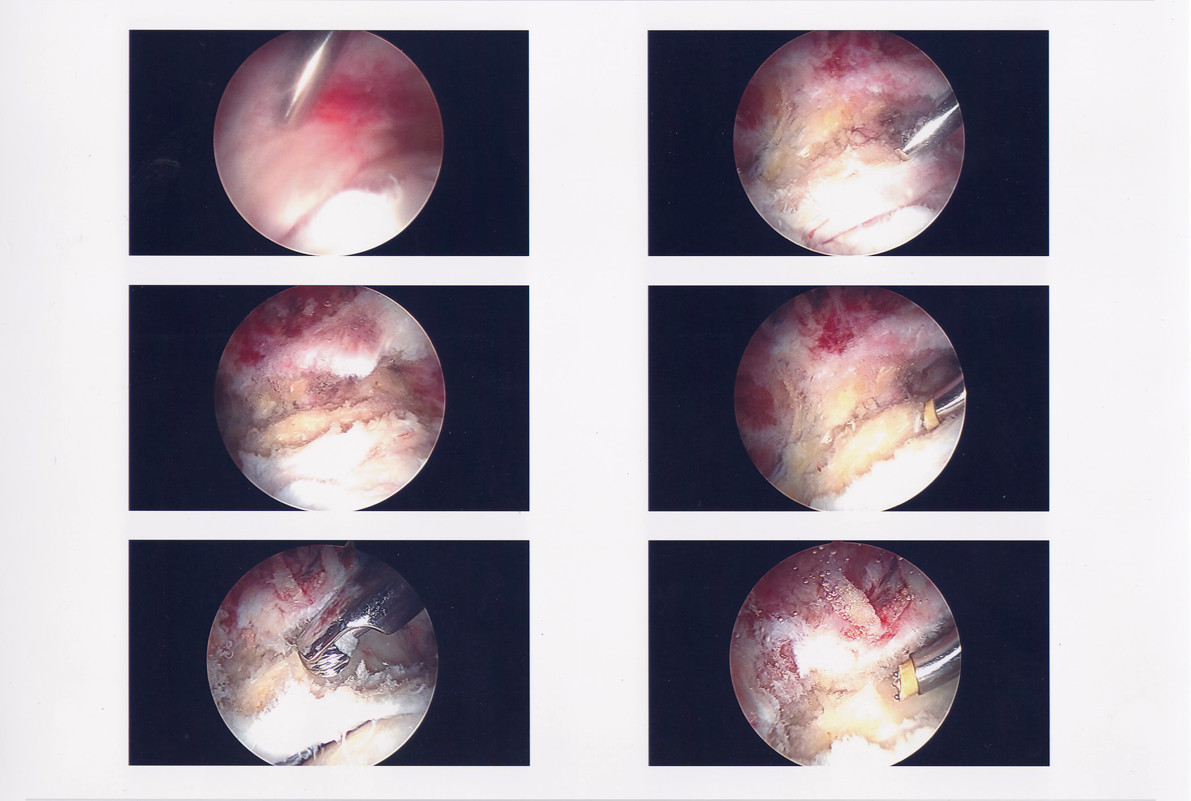

Below is a gallery of the scopes from my surgery. Starting with the initial scope to the Dr. repairing my labrum (if you look at the slide show, it’s the blue thread), then going in and removing the tissue built up in my hip joint and sculpted my hip socket.